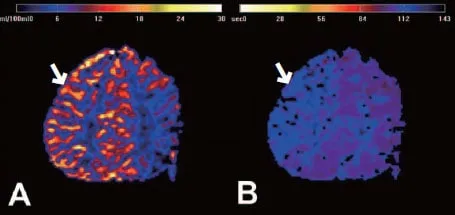

두개 내 양측 내경동맥 말단부위나 주요 가지 동맥의 점차적인 폐쇄로 특징적인 소견을 통해 진단합니다. 뇌 혈관 조영술에서 연기 같은 미세한 혈관들이 관찰되면 모야모야병으로 진단됩니다. 뇌혈역학적 검사(SPECT)를 통해 혈역학적 스트레스 정도를 평가하고 치료 방침을 결정합니다.